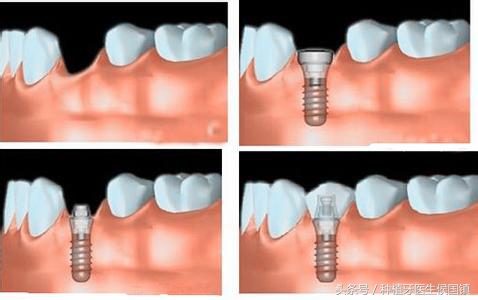

种植牙过程

种植牙